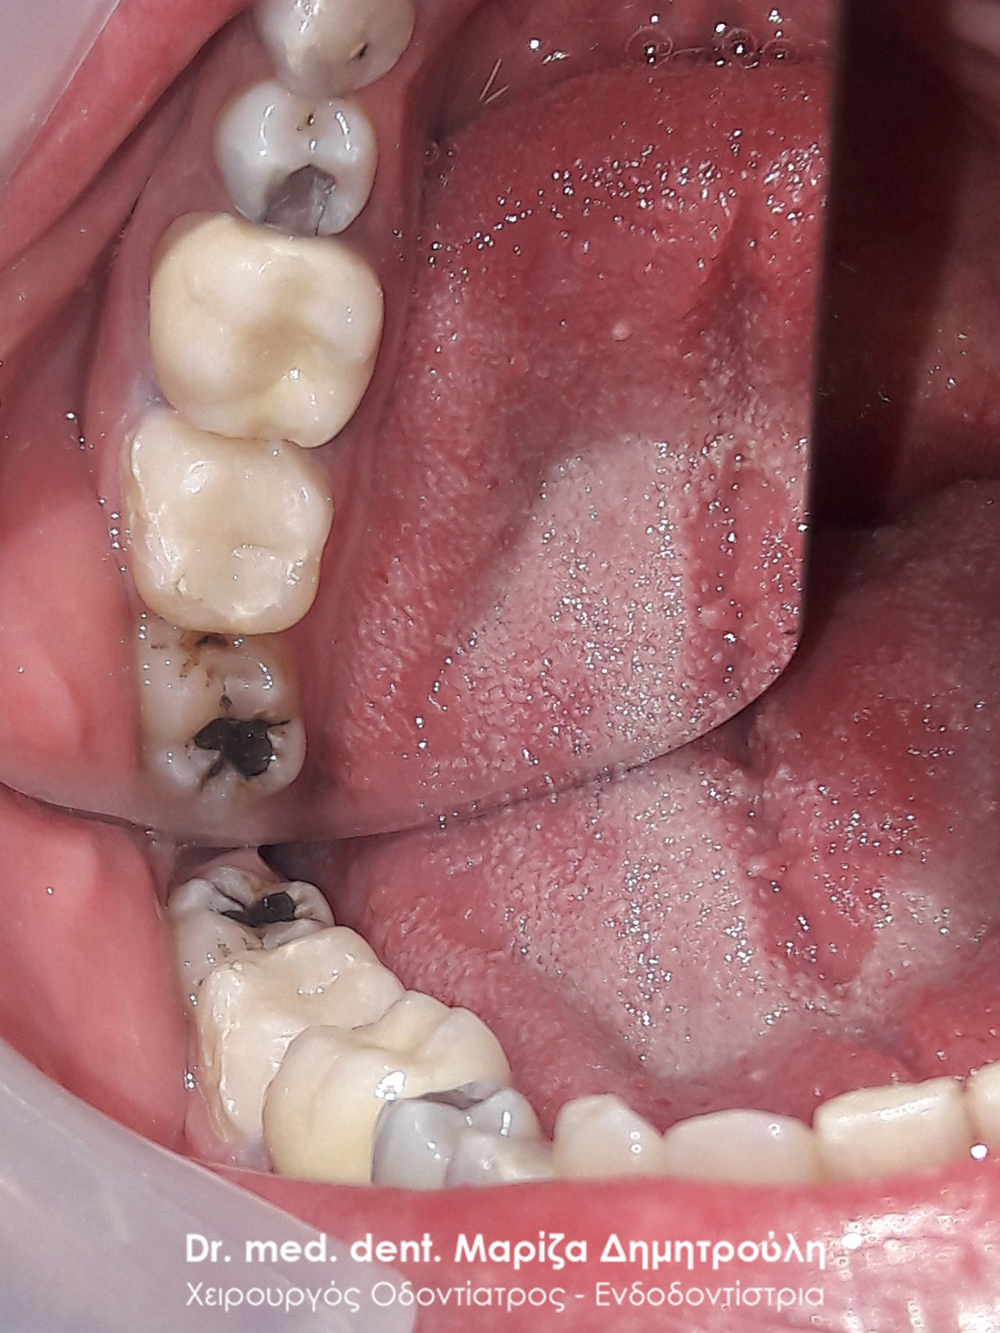

Η ασθενής είχε αντικαταστήσει πριν 2 μήνες 2 σφραγίσματα ( στον 1ο γομφίο και στον 1ο προγόμφιο) στην αριστερή πλευρά της άνω γνάθου. Ανέφερε οτι από τη στιγμή εκείνη υποφέρει από έντονους πόνους. Μετά την κλινική εξέταση διαπιστώθηκε η παρουσία τερηδόνας στο 2ο γομφίο και στο φρονιμίτη. Αποφασίστηκε η αποκατάσταση των τερηδονισμένων δοντιών με λευκά σφραγίσματα σύνθετης ρητίνης. Όσον αφορά τα δόντια με την ευαισθησία πραγματοποιήθηκε αντικατάσταση τους με προσωρινό καταπραυντικό υλικό σφραγίσματος. Σε επόμενο ραντεβού πραγματοποιήθηκε η τελική αποκατάσταση των δοντιών αυτών με λευκά σφραγίσματα ρητίνης.

ΠΡΙΝ

META